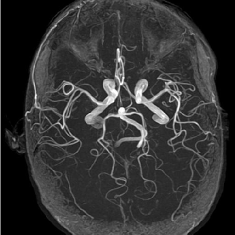

(d) Circle of Willis

Figure 2: Test Images.

We turn now to test TDIHT for high dimensional signals. We test the performance of several MRI images: the Shepp-Logan phantom, FLAIT brain image, T2 Sagittal view of the lumbar spine and the circle of Willis. The first image is of size 256×256256256256\times 256, while the other are of size 512×512512512512\times 512. They are all presented in Fig. 2.